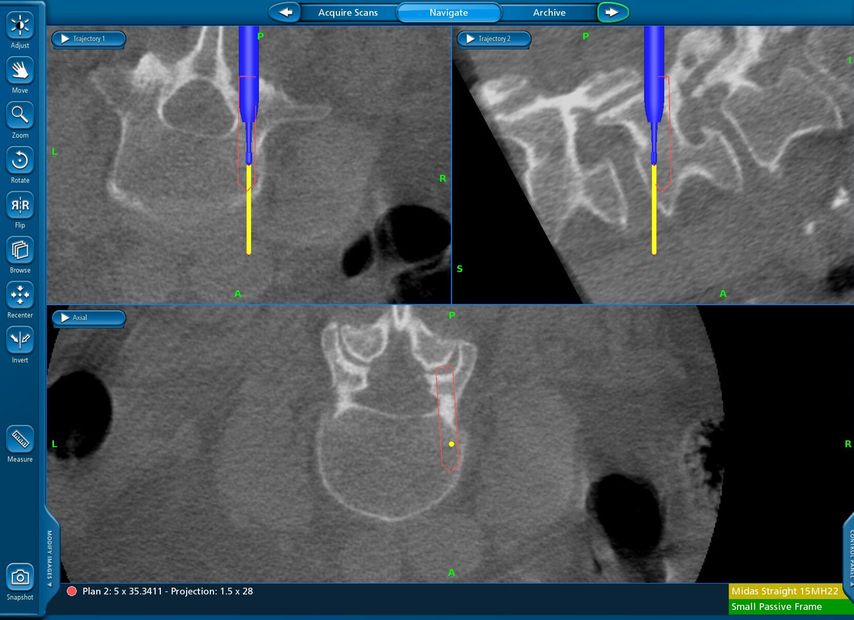

Fallbeispiel 2

TLIF über Mittellinienzugang mit Schrauben in „cortical bone trajectory“. Bei der 63-jährigen Patientin bestand eine degenerative Spondylolisthese Meyerding Grad I mit Facettengelenkszysten und Wirbelkanalstenose (Abb. 8). Klinisch bestanden Lumboischialgien mit Ausstrahlung dem Dermatom L5 bds. entsprechend. Es wurde ein Mittellinienzugang durchgeführt und zuerst wurden navigierte Schrauben in „cortical bone trajectory“ platziert (Abb. 9). Anschließend erfolgten eine Facettektomie L4/5 links und eine Dekompression des Wirbelkanals. Abbildung 10 zeigt, dass der Hautschnitt aufgrund der mittelliniennahen Schraubenköpfe klein gehalten werden kann. Klinisch wurden die lumbalen Schmerzen wie ausstrahlende Beschwerden 1 Jahr postoperativ annähernd vollständig behoben, die korrespondierende Röntgenkontrolle ist in Abbildung 11 dargestellt.